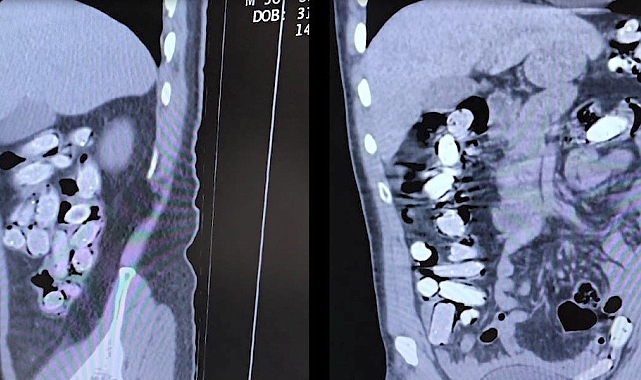

Gözaltına alınan şahıslar, Tatvan Devlet Hastanesine sevk edildi. Burada yapılan röntgen ve tomografi incelemeleri sonucunda, şüphelilerin mide ve bağırsaklarında çok sayıda yabancı cisim tespit edildi. Bunun üzerine şahıslara tıbbi müdahale uygulandı. Müdahale sonucunda, şüphelilerin paketleyerek yuttuğu toplam 96 adet, daralı ağırlığı 1 kilogram 340 gram olan Afyon sakızı ele geçirildi.